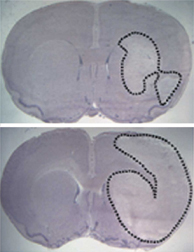

Seeking to uncover neuroglobin’s role, David A. Greenberg of the Buck Institute for Age Research in Novato, Calif., and his colleagues recently induced strokes in rats whose brains had been injected with viruses genetically engineered to churn out the protein. The amount of brain tissue damaged by the strokes was significantly less in those animals than in rats not given the virus, or in rats whose brains had less-than-normal amounts of neuroglobin, the investigators report in the March 18 Proceedings of the National Academy of Sciences.